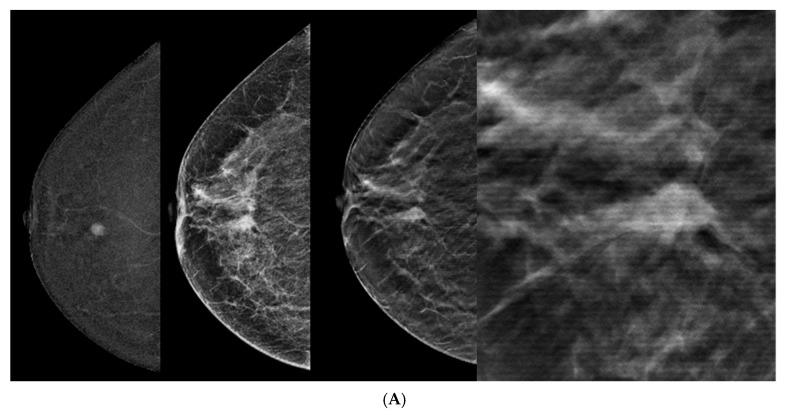

BIRADS scores of CEM-detected lesions were upgraded toward the lesion's pathology with the addition of DBT ( > 0.0001), overall and for each reader. The difference in BIRADS scores before and after the addition of DBT was more significant for readers who were less experienced. The reason for changes in the BIRADS score was better lesion margin visibility. The main BIRADS descriptors applied in the malignant lesions were spiculations, calcifications, architectural distortion, and sharp or obscured margins.

与 CEM 检出病变的 BIRADS 评分相比,添加 DBT 后(>0.0001),总体和每位读者的评分均升高。对于经验较少的读者,添加 DBT 前后 BIRADS 评分的差异更显著。BIRADS 评分变化的原因是更好地显示病变边界。在恶性病变中应用的主要 BIRADS 描述符是分叶状、钙化、结构扭曲和锐利或模糊的边界。